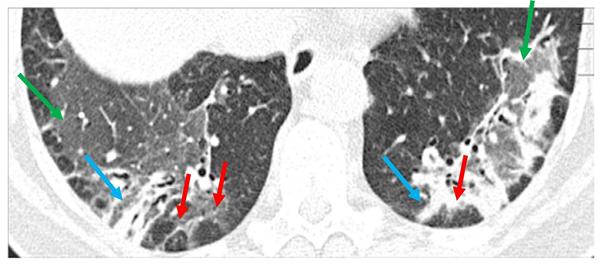

Tuberculose van het centrale zenuwstelsel doet zich in Nederland vooral voor bij mensen uit landen waar tuberculose endemisch is, of bij de ouderen die in hun jeugd besmet zijn geraakt. Een hiv-infectie en immuunsuppressie verhogen het risico. De ziekte kan zich uiten als een subacute meningitis, cerebrale tuberculomen of myelitis/spondylodiscitis. Tuberculeuze meningitis kan ernstig verlopen met sterfte of blijvende schade tot gevolg. Helaas wordt het vaak te laat herkend. Microbiologische diagnostiek van de liquor is ongevoelig, en dikwijls wordt er een waarschijnlijkheidsdiagnose gesteld op basis van het klinische beeld, typische liquorafwijkingen en epidemiologie. De behandeling bestaat uit maandenlange antimycobacteriële behandeling, adjuvante corticosteroïden en soms uit liquordrainage. Tijdens de behandeling kan een paradoxale verslechtering optreden met een toename van de koorts, inflammatie en neurologische en/of radiologische achteruitgang. Dit noopt tot verlengde of hernieuwde immunosuppressie. Als aan tuberculose van het centrale zenuwstelsel wordt gedacht, moet isolatie worden overwogen, omdat veel patiënten ook longafwijkingen hebben en daarmee besmettelijk kunnen zijn.